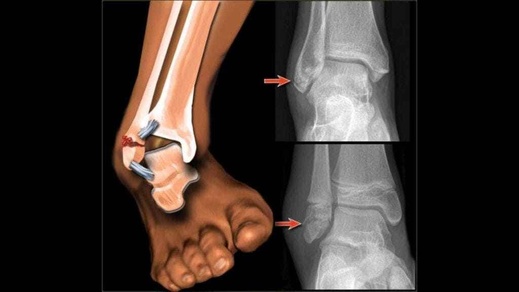

تعرض شاب ينحدر من مدينة بن الطيب، مساء الثلاثاء، لكسر على مستوى الكاحل أثناء ممارسته للرياضة، ليتم نقله على وجه السرعة إلى المستشفى الإقليمي بالدريوش قصد تلقي الإسعافات الضرورية، إلا أن أسرته تفاجأت بإخبارهم بأن الطبيب المختص في جراحة العظام غير متوفر خلال الأيام المقبلة.

ووفق ما أفادت به أسرة المصاب، فقد تم إبلاغهم بأن جدول الطبيب ممتلئ يومي الأربعاء والخميس، على أن يبدأ إجازته الإدارية يوم الجمعة، ما يعني أن إجراء عملية التثبيت الجراحي مستبعد قبل الأسبوع القادم.